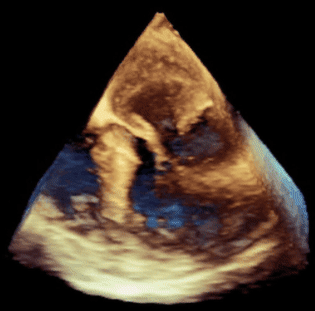

After passing a TEE probe, the following 3D image with 2D projections is obtained. The feature in the right atrium is most likely ...

A.  Foreign body remnant

B.  Vegetation with mobile thrombus

C.  Primitive valve

D.  Chiari network

E.  None of the above

D. This is a combined 3D and 2D transesophageal echo revealing a prominent Chiari network in the right atrium, which a normal variant.